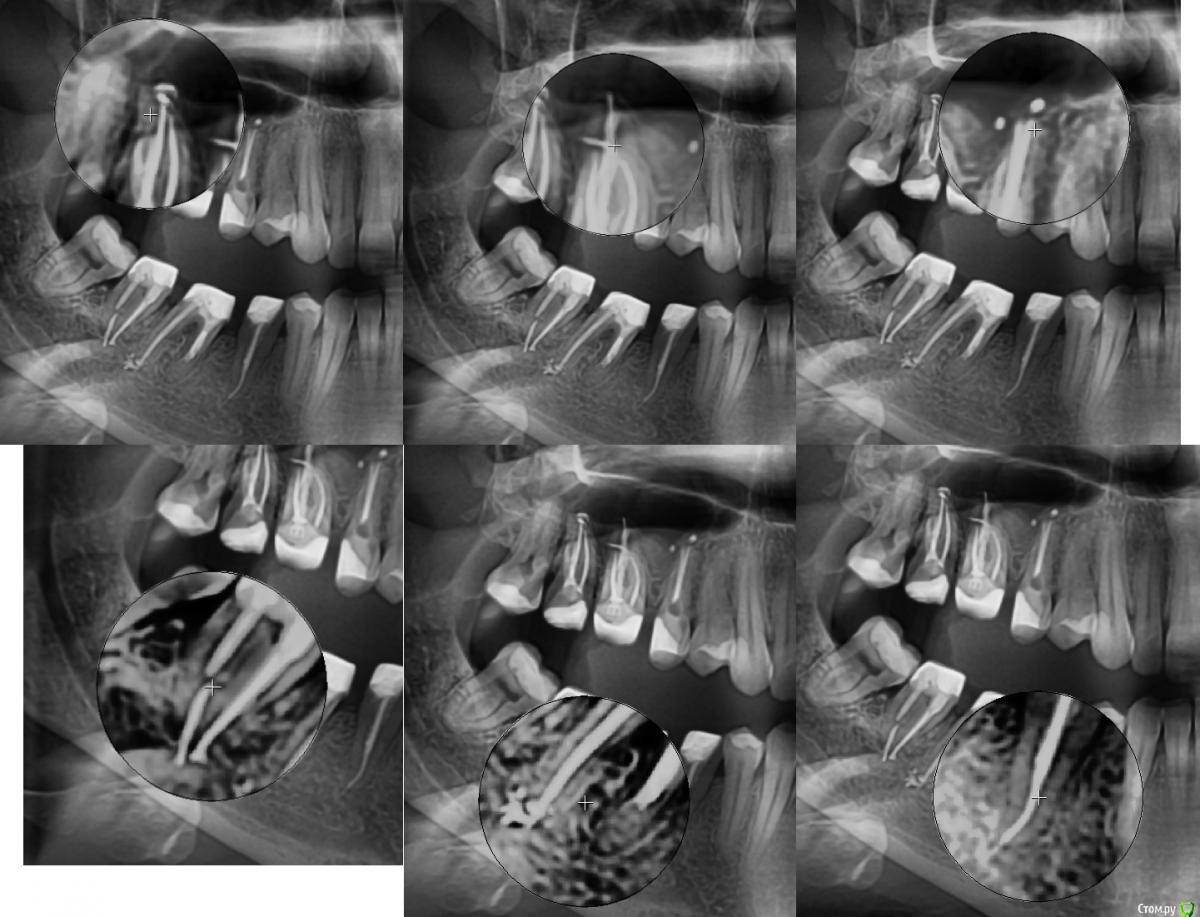

vicTORYa Опубликовано 6 октября, 2016 Автор Поделиться Опубликовано 6 октября, 2016 (изменено) Здравствуйте. Сделала КТ зубное, на 5 нижем правом зубе показалось что есть пятно странное. Подскажите не киста ли это? http://s016.radikal.ru/i337/1610/c3/a4db31326fc5.jpg Изменено 6 октября, 2016 пользователем vicTORYa Ссылка на комментарий

vicTORYa Опубликовано 12 октября, 2016 Автор Поделиться Опубликовано 12 октября, 2016 http://s018.radikal.ru/i513/1610/66/8dc851a309fdt.jpg http://s017.radikal.ru/i442/1610/bf/91e67d17fb96t.jpg http://s020.radikal.ru/i714/1610/00/bc65a4f99070t.jpg http://s017.radikal.ru/i438/1610/e9/60b8a7c730e7t.jpg http://s019.radikal.ru/i611/1610/71/877abc612cbet.jpg http://s020.radikal.ru/i713/1610/cf/c3fea13f9275t.jpg http://i013.radikal.ru/1610/e4/4b10087edaf6t.jpg http://s56.radikal.ru/i154/1610/b1/ac995a59f864t.jpg http://s017.radikal.ru/i440/1610/44/09882ae1e715t.jpg http://s017.radikal.ru/i407/1610/6d/be2fa1c9dde1t.jpg http://s019.radikal.ru/i617/1610/04/455b1edc56b6t.jpg http://s020.radikal.ru/i718/1610/0d/3d2250b2b1a2t.jpg http://s020.radikal.ru/i722/1610/00/3207bd86e2fdt.jpg http://s019.radikal.ru/i635/1610/40/bb734572883ct.jpg http://s017.radikal.ru/i413/1610/56/6e38ec905120t.jpg http://s011.radikal.ru/i318/1610/ca/3f09a02eb2f9t.jpg http://s017.radikal.ru/i429/1610/55/d0b2a1e679dat.jpg http://s016.radikal.ru/i334/1610/49/55e86166b9fdt.jpg http://s020.radikal.ru/i704/1610/c7/12ac17b8751dt.jpg http://s019.radikal.ru/i617/1610/8b/0c40b4ebd10ft.jpg http://s020.radikal.ru/i719/1610/66/d85d7d230523t.jpg http://s017.radikal.ru/i443/1610/20/f6c7e196559at.jpg Ссылка на комментарий

vicTORYa Опубликовано 23 октября, 2016 Автор Поделиться Опубликовано 23 октября, 2016 Скажите пожалуйста понятно ли что-то на этом КТ?С момента их лечения прошло чуть больше года, ждала не ставила коронки посмотреть не дадут ли проблемы зубы, в которых выведен материал, можно ли на данный момент сделать какие-то выводы? 6 и 7 не беспокоят, а вот 5 немного побаливает иногда. Просто иду на следующей неделе ставить коронки, всё ли в порядке с зубами, можно ли ставить коронки? Перелечивать так на всякий случаи не хочется, а только если там возникнет проблема. У мужа тоже есть один зуб с выведенным материалом и ему уже больше 10 лет и нет с ним проблем. Вот и думаю перелечивать только в случае необходимости.Сделать новый ренген не могу очень много уже сделал ренгенов за этот год. Ссылка на комментарий